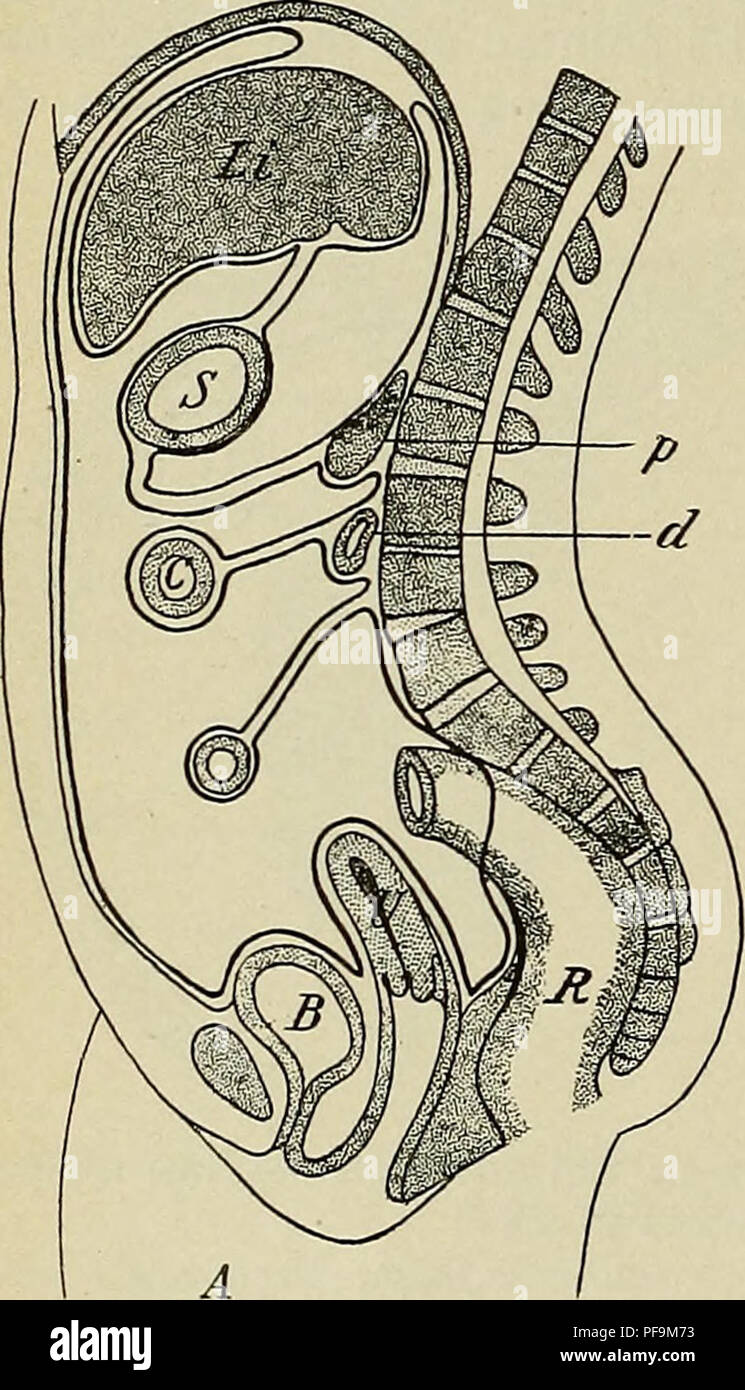

. The development of the human body : a manual of human embryology. Embryology; Embryo, Non-Mammalian. 328 THE PERITONEUM first the attachment of the omentum is vertical, since it represents the mesogastrium, but later, by fusion with the parietal peritoneum, it assumes a transverse direction, while at the same time the pancreas, which originally lay between the two folds of the mesogastrium, is carried dorsally and comes to have a retroperitoneal position in the line of attachment of the omentum. By this change the lower layer of the omentum is brought in contact with the upper layer of the. Stock Photohttps://www.alamy.com/image-license-details/?v=1https://www.alamy.com/the-development-of-the-human-body-a-manual-of-human-embryology-embryology-embryo-non-mammalian-328-the-peritoneum-first-the-attachment-of-the-omentum-is-vertical-since-it-represents-the-mesogastrium-but-later-by-fusion-with-the-parietal-peritoneum-it-assumes-a-transverse-direction-while-at-the-same-time-the-pancreas-which-originally-lay-between-the-two-folds-of-the-mesogastrium-is-carried-dorsally-and-comes-to-have-a-retroperitoneal-position-in-the-line-of-attachment-of-the-omentum-by-this-change-the-lower-layer-of-the-omentum-is-brought-in-contact-with-the-upper-layer-of-the-image215957703.html

. The development of the human body : a manual of human embryology. Embryology; Embryo, Non-Mammalian. 328 THE PERITONEUM first the attachment of the omentum is vertical, since it represents the mesogastrium, but later, by fusion with the parietal peritoneum, it assumes a transverse direction, while at the same time the pancreas, which originally lay between the two folds of the mesogastrium, is carried dorsally and comes to have a retroperitoneal position in the line of attachment of the omentum. By this change the lower layer of the omentum is brought in contact with the upper layer of the. Stock Photohttps://www.alamy.com/image-license-details/?v=1https://www.alamy.com/the-development-of-the-human-body-a-manual-of-human-embryology-embryology-embryo-non-mammalian-328-the-peritoneum-first-the-attachment-of-the-omentum-is-vertical-since-it-represents-the-mesogastrium-but-later-by-fusion-with-the-parietal-peritoneum-it-assumes-a-transverse-direction-while-at-the-same-time-the-pancreas-which-originally-lay-between-the-two-folds-of-the-mesogastrium-is-carried-dorsally-and-comes-to-have-a-retroperitoneal-position-in-the-line-of-attachment-of-the-omentum-by-this-change-the-lower-layer-of-the-omentum-is-brought-in-contact-with-the-upper-layer-of-the-image215957703.htmlRMPF9M73–. The development of the human body : a manual of human embryology. Embryology; Embryo, Non-Mammalian. 328 THE PERITONEUM first the attachment of the omentum is vertical, since it represents the mesogastrium, but later, by fusion with the parietal peritoneum, it assumes a transverse direction, while at the same time the pancreas, which originally lay between the two folds of the mesogastrium, is carried dorsally and comes to have a retroperitoneal position in the line of attachment of the omentum. By this change the lower layer of the omentum is brought in contact with the upper layer of the.